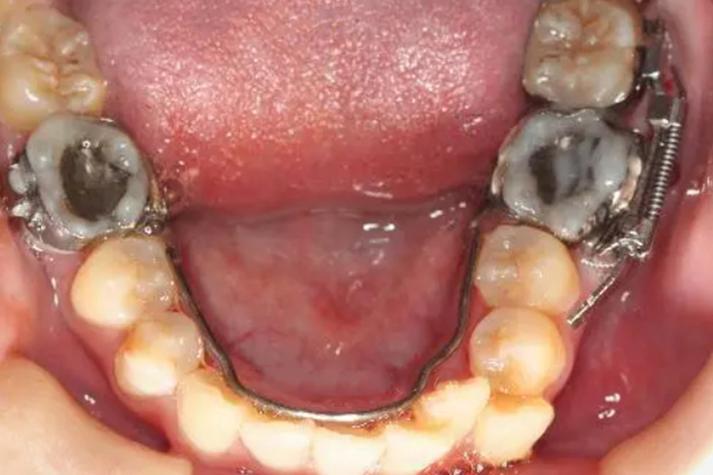

滑动杆装置:由横腭杆、舌弓及滑动杆组成,通过滑动杆的滑动带动磨牙远中移动,常用于上颌磨牙,可同时控制磨牙的垂直向位置,防止伸长或压低。

可摘式推磨牙矫治器:如Jasper Jumper装置,通过弹性连接体连接磨牙与前牙区,利用颌骨的肌肉力量间接推动磨牙,适合青少年,可利用生长发育潜力,但需定期调整。